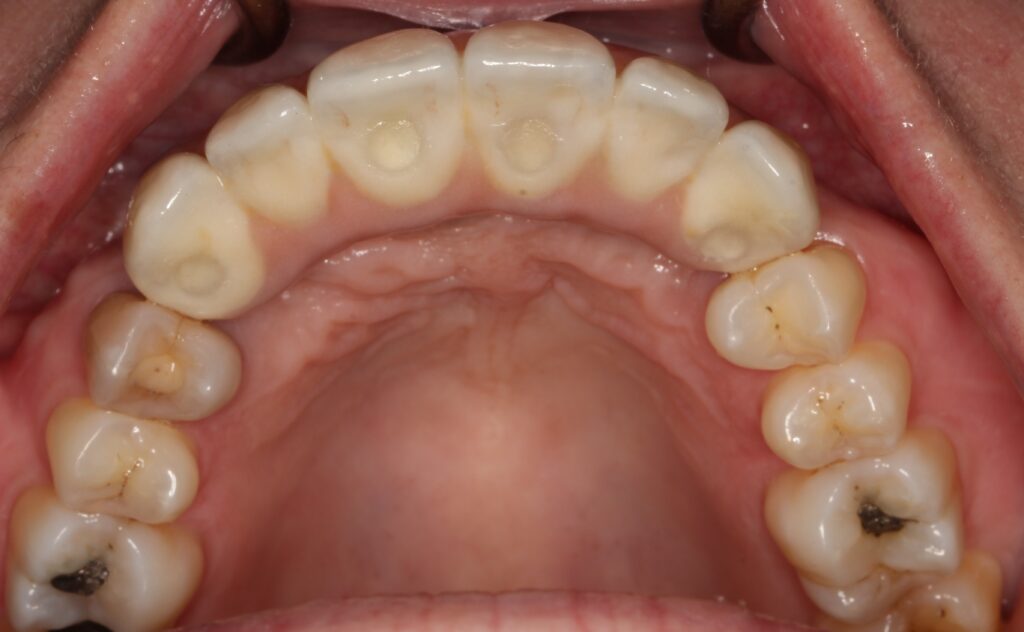

A selection of partial arch fixed implant bridge patients